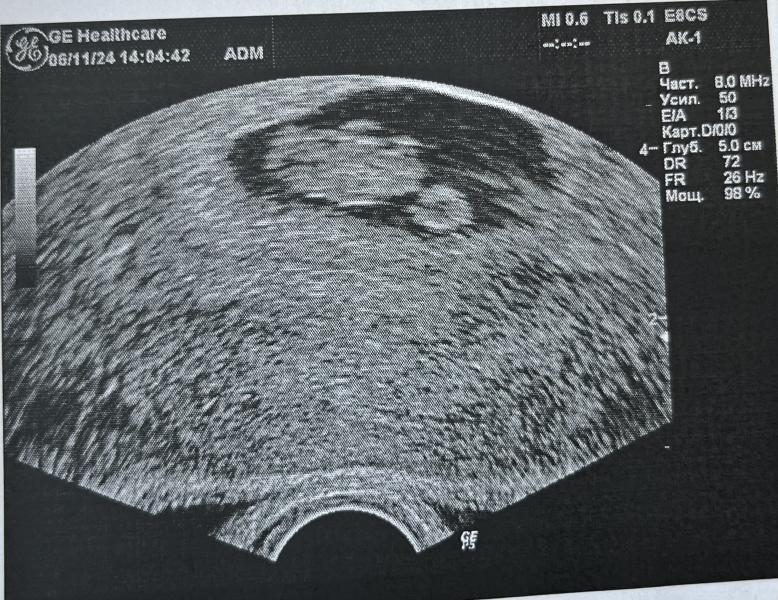

Первое УЗИ при беременности: 7 недель и 3 дня - все в порядке, сердечко бьется! Срок соответствует?

Первое УЗИ.😍Все хорошо, сердечко бьется, срок поставили 7недель3дня🐣. Разница в неделю.

06.11.2024